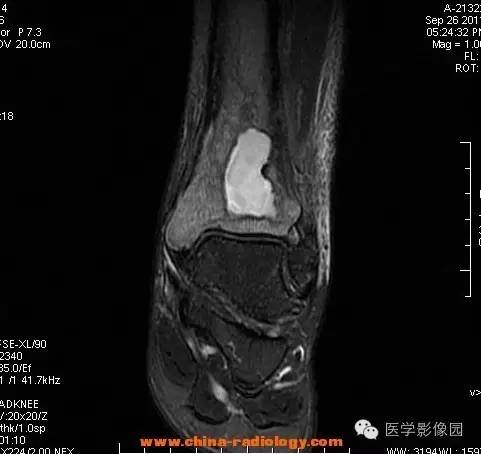

【病例】胫骨骨脓肿1例MR影像表现

影像学表现:胫骨中下段干骺端不未规则形长T1长T2信号,T2WI见不完整环形稍低信号影,T2脂肪抑制低信号更明显,并见胫骨下段及踝关节后外侧软组织呈弥漫稍高信号,增强明显不均匀强化,增强见低信号环内有环形强化影。

影像学表现:表现为长骨干骺端有椭圆形密度减低区,边缘有清晰的骨质硬化,病变与邻近正常骨髓腔境界清楚。MRI上T1WI呈低信号,少数呈等信号,T2WI多为混杂高信号,增强扫描可见环状强化,强化的脓肿壁薄而均匀。